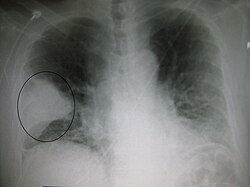

Rentgeninis plaučių tyrimas